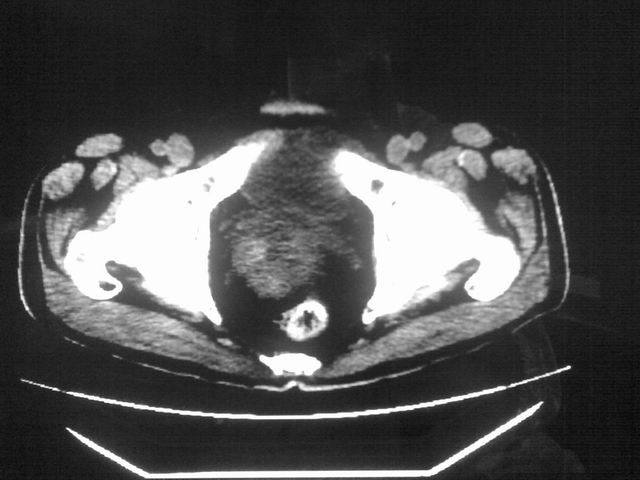

患者m 56岁,盆腔及下腹部胀痛半年,加重1月余,消瘦\中重度贫血.(附:平扫时直肠的高信号为,残留的钡剂).补一下病史:胃镜及纤维结肠镜均无明显异常.

首先是病灶的定位,平扫看很象肠管肿瘤但既然纤维结肠镜正常就可以除外结肠病变,增强成不均匀强化,位于右下腹部应该首先考虑回肠末段占位性病变,1淋巴瘤,2间质瘤,3腹膜后神经原肿瘤待除外,

首先是病灶的定位,平扫看很象肠管肿瘤但既然纤维结肠镜正常就可以除外结肠病变,增强成不均匀强化,位于右下腹部应该首先考虑回肠末段占位性病变,以间质瘤或淋巴瘤可能性大.,

膀胱及直肠间有不规侧的软组织密度影,内密度不均匀。其内有坏死囊变,前列腺及精囊腺,膀胱后壁受浸。结合病史考虑腹膜后肉瘤可能性大。